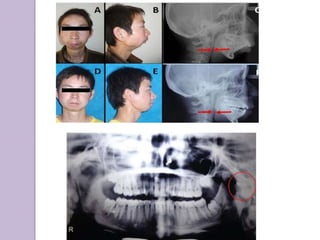

Juvenile Chronic Arthritis(JCA)

Stillโ€™s Disease, Juvenile Rheumatoid

Arthritis

Synovial hypertrophy,

joint effusion &

swollen painful joints

Associated splenomegaly,

lymphadenopathy, leukocytosis,

pyrexia and rash

TMJ involvement in

40%

Chronic inflammatory disease

that appears before 16 years

Bilateral polyarthritis of both

small and large joints including

cervical spine

Severe TMJ involvement

results inhibition of

mandibular growth causing

micrognathia

When one joint is severely

affected โ€“mandibular

asymmetry โ€“ deviated to

affected side

RADIOGRAPHICALLY:

Erosion of condyle

Deepened antegonial

notch

Bending of ramus and

condylar head

Osteopenia